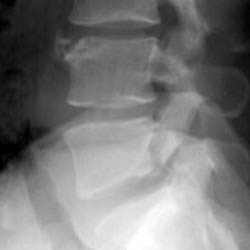

Skeletal Trauma > Lumbar Spine > Quiz

Thoracic and Lumbar Spine Quiz

True or False 1. Wedge fractures are unstable. 2. CT should be performed in most fracture cases. | ||||